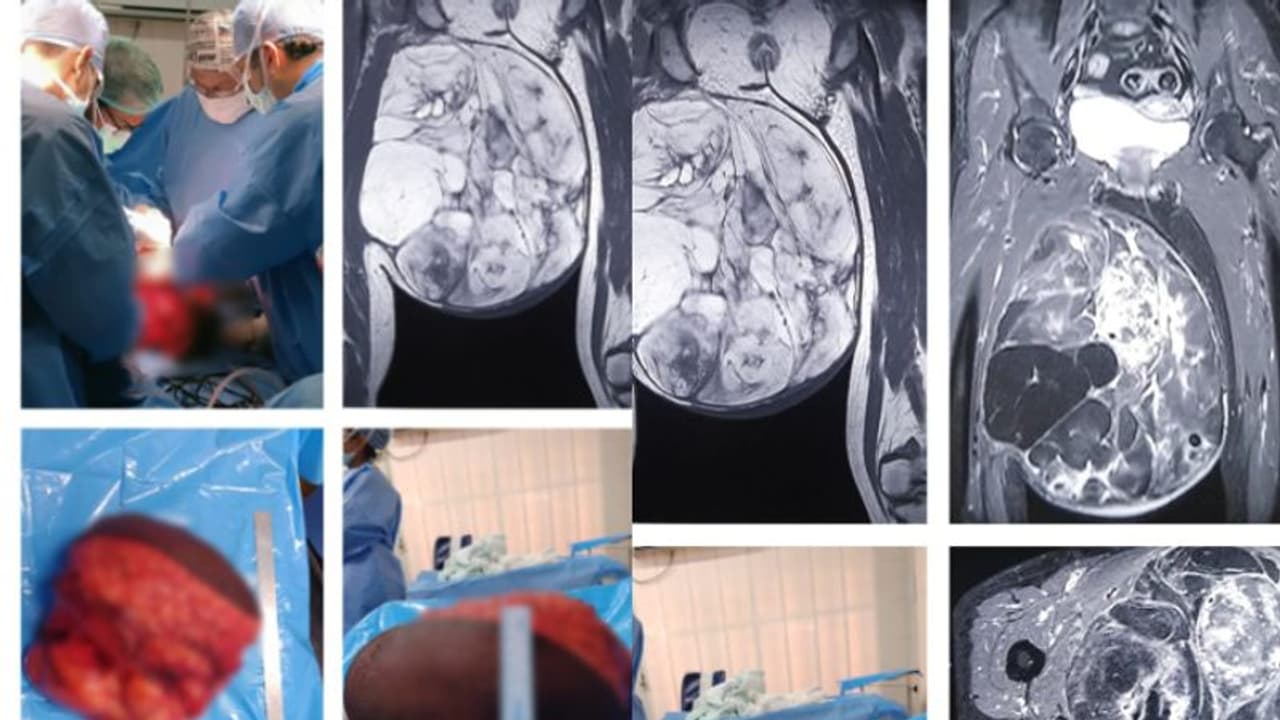

തൃശൂർ: 10 കിലോ ഭാരമുള്ള മുഴ കാരണം നടക്കാന് കഴിയാതെ വന്ന 61കാരിയ്ക്ക് ആശ്വാസമേകി തൃശൂര് മെഡിക്കല് കോളേജ്. 6 മണിക്കൂര് നീണ്ട ശസ്ത്രക്രിയയിലൂടെ കാലില് നിന്നും ട്യൂമര് നീക്കം ചെയ്തു. കാലില് തുടയോട് ചേര്ന്ന് അതിവേഗം വളര്ന്ന 10 കിലോഗ്രാം ഭാരമുള്ള ട്യൂമര് സങ്കീര്ണ ശസ്ത്രക്രിയയിലൂടെ നീക്കം ചെയ്ത് തൃശൂര് സര്ക്കാര് മെഡിക്കല് കോളേജ്. ട്യൂമര് മൂലം നടക്കാന് പോലും ഏറെ ബുദ്ധിമുട്ടിരുന്ന 61 വയസുള്ള തൃശൂര് പുഴക്കല് സ്വദേശിനിക്കാണ് ശസ്ത്രക്രിയ നടത്തിയത്.

ഹെപ്പറ്റെറ്റിസ് രോഗം കൂടി ഉണ്ടായിരുന്നത് ശസ്ത്രക്രിയയുടെ സങ്കീര്ണത വര്ധിപ്പിച്ചിരുന്നു. വിജയകരമായ ശസ്ത്രക്രിയയ്ക്ക് ശേഷം രോഗിക്ക് സാധാരണ പോലെ നടക്കാനായത് പുനര്ജീവനമായാണ് രോഗിയും ബന്ധുക്കളും കരുതുന്നത്. മെഡിക്കല് കോളേജിലെ സര്ജറി വിഭാഗവും ഓങ്കോ സര്ജറി വിഭാഗവും ചേര്ന്നാണ് ശസ്ത്രക്രിയ നടത്തിയത്. ശസ്ത്രക്രിയയ്ക്ക് നേതൃത്വം നല്കിയ മുഴുവന് ടീമിനേയും ആരോഗ്യ വകുപ്പ് മന്ത്രി വീണാ ജോര്ജ് അഭിനന്ദിച്ചു. ഒരു മാസം മുമ്പാണ് നടക്കാന് പോലും കഴിയാതെ കാലില് വലിയ മുഴയുമായി 61 വയസുകാരി മെഡിക്കല് കോളേജ് ആശുപത്രിയിലെത്തുന്നത്. വിദഗ്ധ പരിശോധനയില് ട്യൂമര് ആണെന്ന് ബോധ്യപ്പെട്ടു.

കാലില് തുടയോട് ചേര്ന്ന് അതിവേഗം വളര്ന്ന 30x30x15 സെന്റീമീറ്റര് വലിപ്പമുള്ള ട്യൂമറായിരുന്നു. കൂടാതെ രോഗിക്ക് ഹെപ്പറ്റെറ്റിസ് ഉണ്ടായിരുന്നതിനാല് അധിക മുന്കരുതലുകള് കൂടിയെടുത്തു. ഈ മാസം പത്താം തീയതിയാണ് ശസ്ത്രക്രിയ നടത്തിയത്. ആറു മണിക്കൂര് നീണ്ടുനിന്ന ശസ്ത്രക്രിയയിലൂടെയാണ് കാലിലേക്കുള്ള രക്തക്കുഴലുകള്, നാഡീഞരമ്പുകള് എന്നിവയ്ക്ക് ക്ഷതമേല്ക്കാതെ 10 കിലോ തൂക്കവും 30x30x15 സെന്റീമീറ്റര് വ്യാപ്തിയുമുള്ള, സോഫ്റ്റ് ടിഷ്യൂ സാര്ക്കോമ നീക്കം ചെയ്തത്.

രോഗി സുഖം പ്രാപിച്ചപ്പോള് അടുത്തഘട്ട ചികിത്സയ്ക്കായി റേഡിയോതെറാപ്പി വിഭാഗത്തിലേക്ക് മാറ്റുകയും, ഫിസിയോതെറാപ്പി വിഭാഗത്തിന്റെ കൂടി ഇടപെടലോടെ കാലിലെ പേശികളുടെ തളര്ച്ച പരമാവധി കുറച്ചുകൊണ്ട് സാധാരണ ജീവിതത്തിലേക്ക് തിരിച്ചു വരികയും ചെയ്തിരിക്കുന്നു. സ്വകാര്യ മേഖലയില് ലക്ഷക്കണക്കിന് രൂപ ചെലവ് വരുമായിരുന്ന ഈ ശസ്ത്രക്രിയ സര്ക്കാരിന്റെ വിവിധ സ്കീമുകളില് ഉള്പ്പെടുത്തി സൗജന്യമായാണ് ചെയ്തത്.